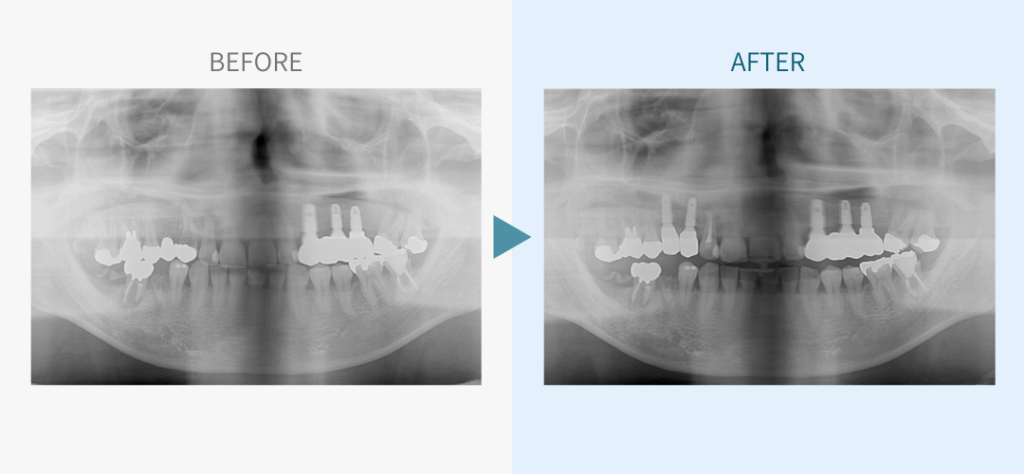

デンタルチームジャパンでは、サイナスリフト(上顎洞底挙上術)や骨造成など、他院で「骨が足りない」と断られた難症例にも対応しています。

私たちは、難症例に関する治療法を学会でも発表しており、その豊富な実績と技術力が評価され、全国から患者様が来院いただいております。

こちらではその一部の症例についてご紹介します。